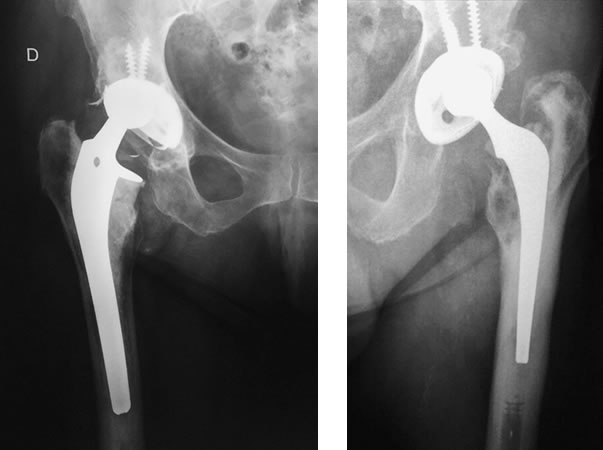

Las indicaciones incluyen: Aflojamiento doloroso aséptico (no infectado) de uno o ambos componentes, fractura o fracaso del implante, Luxación recidivante, artroplastía infectada, fractura periprotésica, etc.

El aflojamiento doloroso de uno o ambos componentes es una complicación a largo plazo. La duración o vida útil de una prótesis de cadera es multifactorial. Los controles traumatológicos así como también los hallazgos radiográficos en el postoperatorio son de gran importancia para el diagnóstico y el tratamiento adecuado.

Es de vital importancia diferenciar entre aflojamiento mecánico y aflojamiento séptico (infectado). El aflojamiento sépitco se discute en la sección Tratamiento de Infecciones